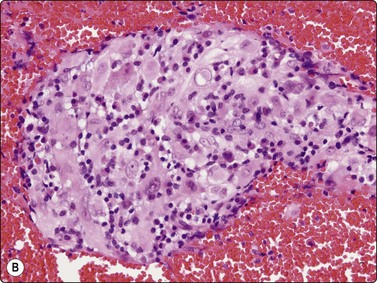

image image image

Fig. 8.28 High-grade neuroendocrine carcinoma; small cell carcinoma

(A, B) Smears showing ‘intermediate’ morphology. Loose aggregates of fragile cells with traumatization artifact and nuclear molding but some background cytoplasm (A, Pap, MP; B, H&E, HP). (C) Tissue section of resected peripheral stage 1 small cell carcinoma (H&E, HP).

image image image image image

Fig. 8.29 High-grade neuroendocrine carcinoma

Variable morphology including small cell and large cell patterns. (A) Low-power smear appearances of small cell carcinoma; (B) Higher-power examination shows some large cells with prominent nucleoli (A, H&E, LP; B, H&E, MP). (C,D) Tissue sections of resected peripheral stage 1 tumor showing areas of geographic necrosis and a predominance of large cells with prominent nucleoli (C, tissue section, H&E, LP, Inset, HP; D, tissue section, H&E, HP). (E) Positive immunostaining for chromogranin in resected specimen (E, tissue section, IPOX, HP).

Criteria for diagnosis

Small or medium-sized cells with little or no cytoplasm (larger than in sputum),

Dispersed cell presentation; some clusters, including some small tight groups,

Nuclear molding and engulfment; irregular nuclei,

Uniform finely or coarsely granular nuclear chromatin; small nucleoli,

Tear-drop cells, smeared cells and streaks of nuclear material,

Engulfment of apoptotic bodies,

Numerous mitotic figures.

This group of lung carcinomas is the most aggressive of the common types, having a mean survival of less than 6 months without treatment. Small cell carcinoma is virtually unheard of in non-smokers, while for carcinoid and atypical carcinoid the smoking association is much weaker. It is important to categorize this neoplasm accurately because, in general, chemotherapy rather than surgery will be used in management. In addition, chemotherapy regimens are different from those used for inoperable non-small cell carcinomas. This group is fairly homogeneous in terms of its biology but is more heterogeneous morphologically. Attempts at morphological subclassification have been made; however, the larger ‘intermediate’ and smaller ‘oat cell’ subtypes are not reliably separable by expert pathologists and do not have significantly different behavior or response to therapy. The latest WHO classification therefore does not subcategorize small cell carcinoma although it does recognize mixtures with other types of carcinoma.217

Cell pleomorphism is so distinctive that a diagnosis of malignancy is seldom in doubt (Figs 8.25-8.27). The most immediate impression is the absence or sparseness of cytoplasm rather than the small size of the neoplastic cell (Figs. 8.26 and 8.27). In fact, the cell nuclei may appear larger than similar cells in sputum and this may mislead one into making a diagnosis of non-small cell carcinoma. This difference in size between sputum and aspirated material is due to degenerative changes and shrinkage in sputum. It is sparseness of cytoplasm rather than size which is the most helpful initial clue in differentiating the lesion from other pulmonary carcinomas.

The combination of dispersal with clustering is also important, especially when other small cell neoplasms enter the differential diagnosis (Fig. 8.25). Lymphomas generally do not display such cell cohesion, although large fragments may be dislodged, and in some cases lymphoid cells may form clusters or packets.

Fragility of nuclei is emphasized by tear-drop cells or streaks of smeared nuclear material,226 and the close nuclear apposition and molding so commonly seen in sputum are also evident (Figs 8.26 and 8.27). Uniform coarsely granular ‘salt and pepper’ nuclear chromatin is also a well-recognized feature of this cancer in other sites, but one point of difference from sputum is the frequency of small nucleoli in aspirated material; they are less commonly seen in sputum. This may also be related to the better preservation of cells removed directly from tumor; small nucleoli are also often seen in bronchial brush material. Mitotic figures are usually easily found.

Although ‘intermediate’ small cell carcinoma is no longer recognized as a separate category in international classifications, we find it a useful concept to highlight the occasional difficulty in distinguishing between small cell and poorly differentiated non-small cell carcinomas (Figs 8.28 and 8.29). There is overlap in nuclear size between small and large cell carcinomas and a tendency for inexperienced cytologists to include small cell carcinomas with larger than expected nuclei in the non-small cell category. In general, if the nuclear features of a problematical tumor are those of small cell carcinoma – that is, granular chromatin without prominent nucleoli – the neoplasm will usually fall into the small cell carcinoma group histologically, whereas vesicular nuclei with prominent nucleoli would generally be evidence of non-small cell tumor. However, large cell neuroendocrine carcinoma does provide special problems. Our experience is limited but is similar to Yang et al. who described various morphologic patterns in this family of tumors, including small cell-like and mixed small cell/large cell-like FNAC patterns.37 Cell size is therefore an important criterion and one to be critically evaluated. Tumors with nuclei larger than 2–3 times the diameter of a lymphocyte may be classified as LCNEC histologically, even if nuclear chromatin pattern and other cytological features are similar to those of small cell carcinoma (Fig. 8.29). Our approach is therefore to first come to a diagnosis of ‘high-grade neuroendocrine carcinoma’ and then to critically examine cell size and morphology to determine the best category – ‘small’ or ‘large’. We do, however, agree with the idea propounded by Marchevsky et al.89 that the distinction between the two categories may be somewhat artificial in view of the overlap in cell size between the two groups. This is an area which requires close cooperation with oncologists and an acceptance of the limitations of cytological diagnosis. It may be necessary to base management on clinical and staging findings in conjunction with inconclusive cytological tumor typing in some cases.